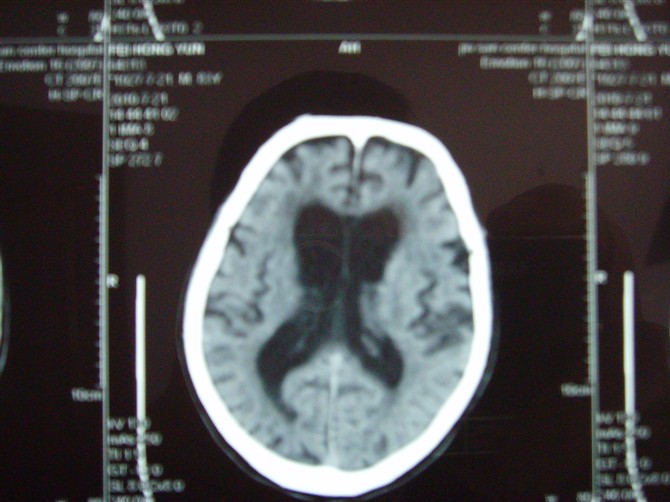

标题: CT27993:男 83岁 头晕伴双下肢无力一天 [打印本页]

标题: CT27993:男 83岁 头晕伴双下肢无力一天

脑白质疏松症,脑萎缩,复查

脑萎缩。伴小脑齿状核、苍白球钙化.脑白质脱髓鞘病变

脑白质疏松症,脑萎缩!

脑萎缩,脑白质疏松症。

1)双侧小脑半球脑软化灶。2)全脑萎缩。3)脑白质病。